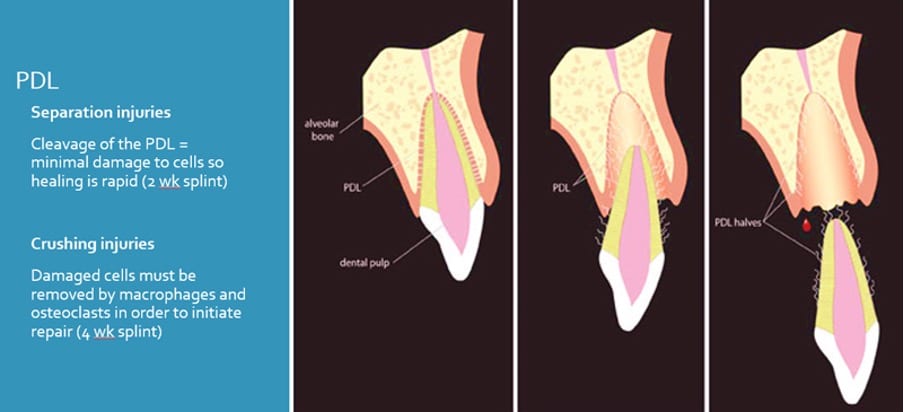

Splinting

Ideal requirements

- Secure

- Easily applied and removed

- Stabilise tooth in correct position

- Allow physiologic tooth mobility

- Allow pulp sensibility testing and endodontic access

- Allow adequate OH

- Avoid interference with occlusal movements

- Provide comfort

Types

- Composite and wire*

- Orthodontic wire and bracket*

- Fibre splints (Everstick)*

- Titanium trauma splints

- Composite splints

- Suck-down splints

- Buccal (usually)

- Flexible (0.016” SS wire)

- Passive

- One non-traumatized tooth either side of affected tooth/teeth

- Keep away from gingival margin